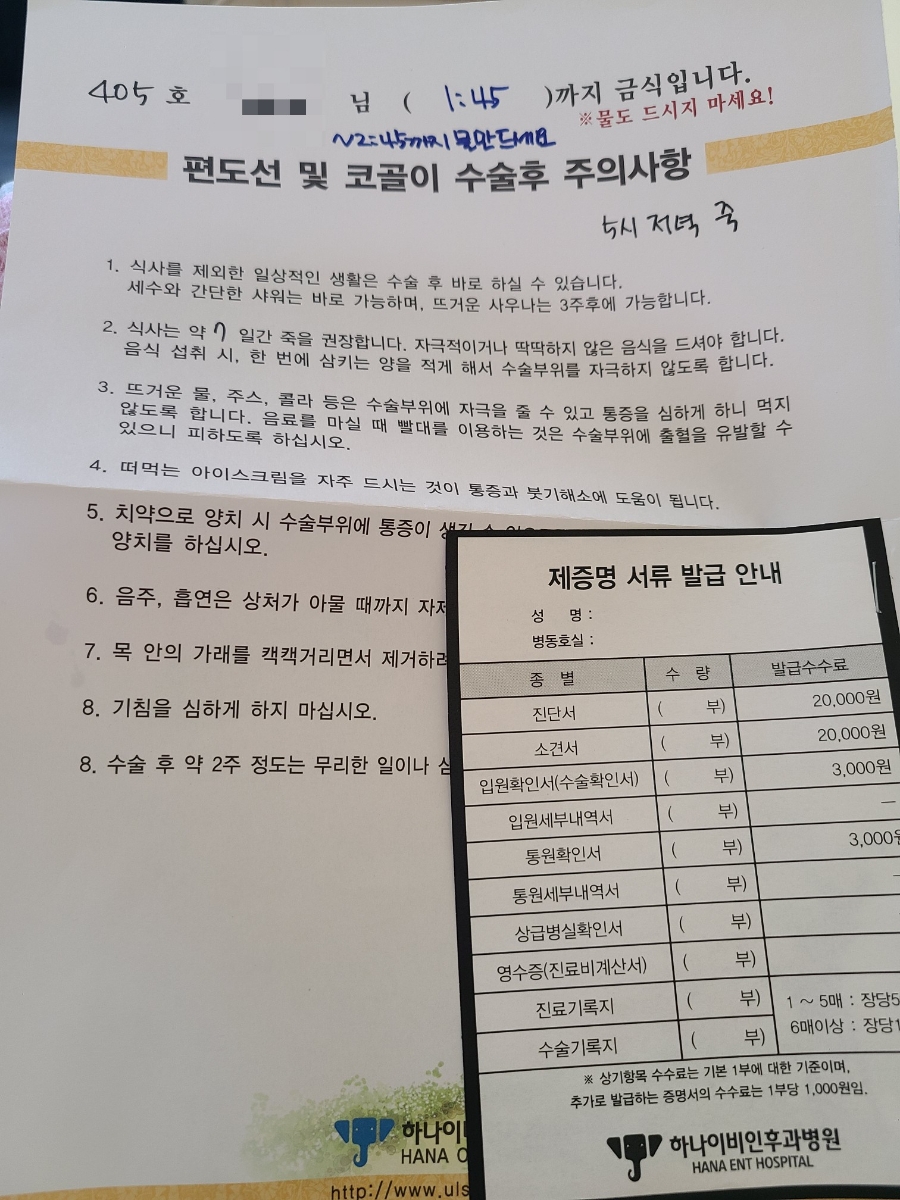

D-day (1/29) 통증의 정도 – 손술 직후 : 2/10 – 총점 : 2/10 (삼킬 때 귀까지 아프지만 견딜 수 있다, 무통)

바꾸길 잘했다 바꿔서 그들은 어떻게 움직여도 하나도 아프지 않아!! 멍을 들었다. 나의 수술 예정 시간은 오전 9시.8시 30분까지 학부모 한 명이 상주해야 해서 어제 생일의 주인공인 엄마를 불렀다.8시 50분쯤 간호사가 5층 수술실로 가자고 했다. 걸어서 엘베타고행 회복실 앞에서 기관지를 확장시키는 흡입기 같은 것을 1분 동안 하라고 해서 했다.다 하고 5분정도 기다리면 수술실에서 저를 부르셔서 어머니와 헤어져 그대로 입실.수술실은 생각보다 작았다.수술상도 다 차려져 있더라.누워서 준비하고 있으면 마취과 원장이 와서 졸릴 것 같아요~라며 마취가스를 뿌렸지만 두 번 정도 마시고 나서 정신을 차려보니 회복실이었다.옆에 어머니가 앉아 있었다.조금 몽롱했지만 어머니에게 했던 이야기가 모두 생각난다. 와, 바로 기절했어 수술실이 생각보다 작다… 이런 얘기. 걸을 수 있을 것 같아서 일어났는데 제지 당해서 침대째 병실로 왔다.병실에 온 시간은 9시 40분?50분 정도였다.1시간도 안 걸렸네.병실에 오자마자 간호사 선생님이 혈압, 체온 등을 재서 거울에 편도선이 사라진 것을 확인하고 엄마가 입속 사진을 찍어달라고 했어ㅋㅋㅋㅋㅋㅋㅋㅋ

드디어 13시 45분!얼음을 띄운 찬물을 마셔보았다. 아프긴 아프지만 참기에 충분했다.이 정도 통증만 있으면 될텐데. 수많은 후기를 읽다 보면 첫째 날에 가장 아픈 사람은 없고 점점 아파오는 것이 공통점이다. 무통도 받고 있으니 이 정도겠지? 안아플때 되도록 많이 먹고 마셔두기로 결심했어.